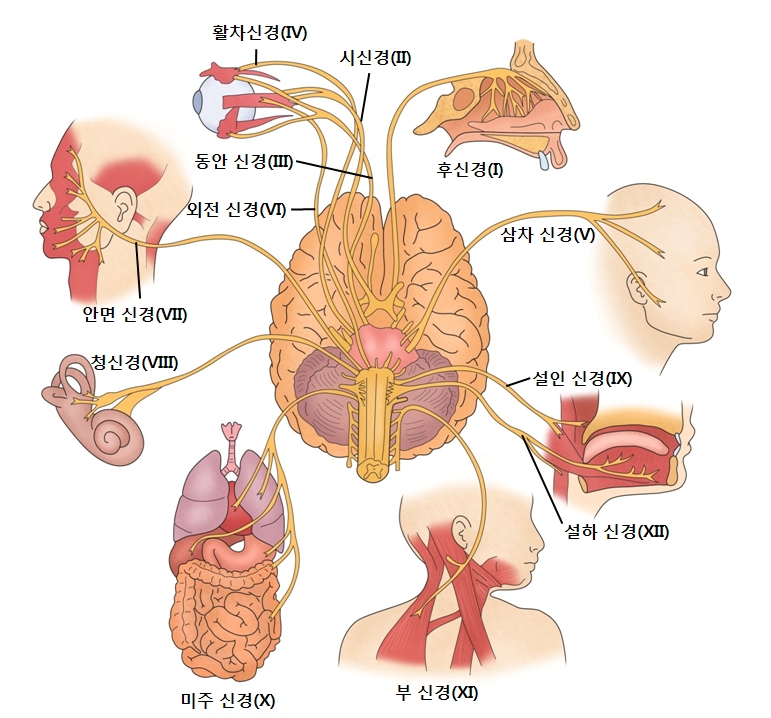

뇌 신경

뇌로부터 나오는 말초신경을 말하며 12쌍이 있습니다.